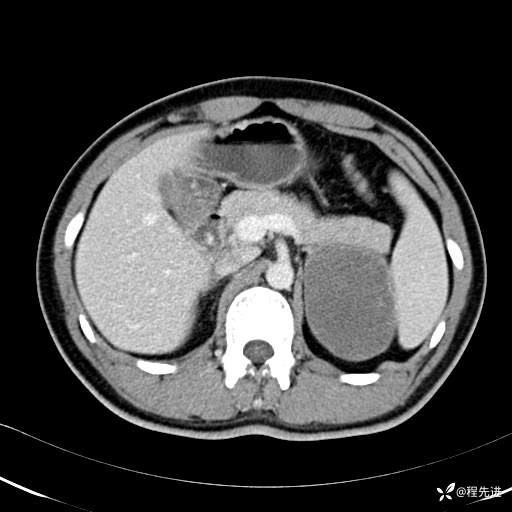

CT平扫:(CT值:平扫,27HU,动脉期,27HU,门静脉期,31HU,平衡期,32HU)